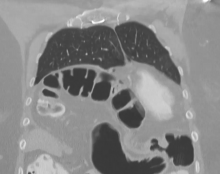

A 57-year-old woman, with a history of pericardiectomy 20 years before, reported progressive dyspnea and orthopnea. A chest computed tomography scan showed a large anterior diaphragmatic (Morgagni) hernia containing a loop of transverse colon and omentum producing mass effect on the right atrium and ventricle. Significant right ventricular outflow obstruction and a small loculated pericardial effusion were confirmed on cardiac magnetic resonance imaging. A sniff test suggested minimal to no motion of the right hemidiaphragm.